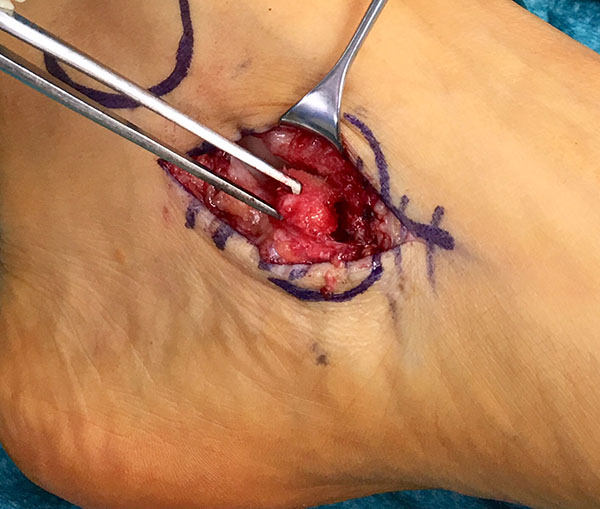

Direkte Traumazeichen wie ein Hämatom oder eine ausgeprägte Schwellung treten üblicherweise nicht auf, wobei vereinzelt auch bei einem adäquaten Trauma ein vollständiger Ausriss des Os tibiale externum beobachtet werden kann (Abb. 1).

Zum Lesen der Bildbeschreibung und zur Vollansicht bitte das Bild anklicken. Foto: Markus Walther